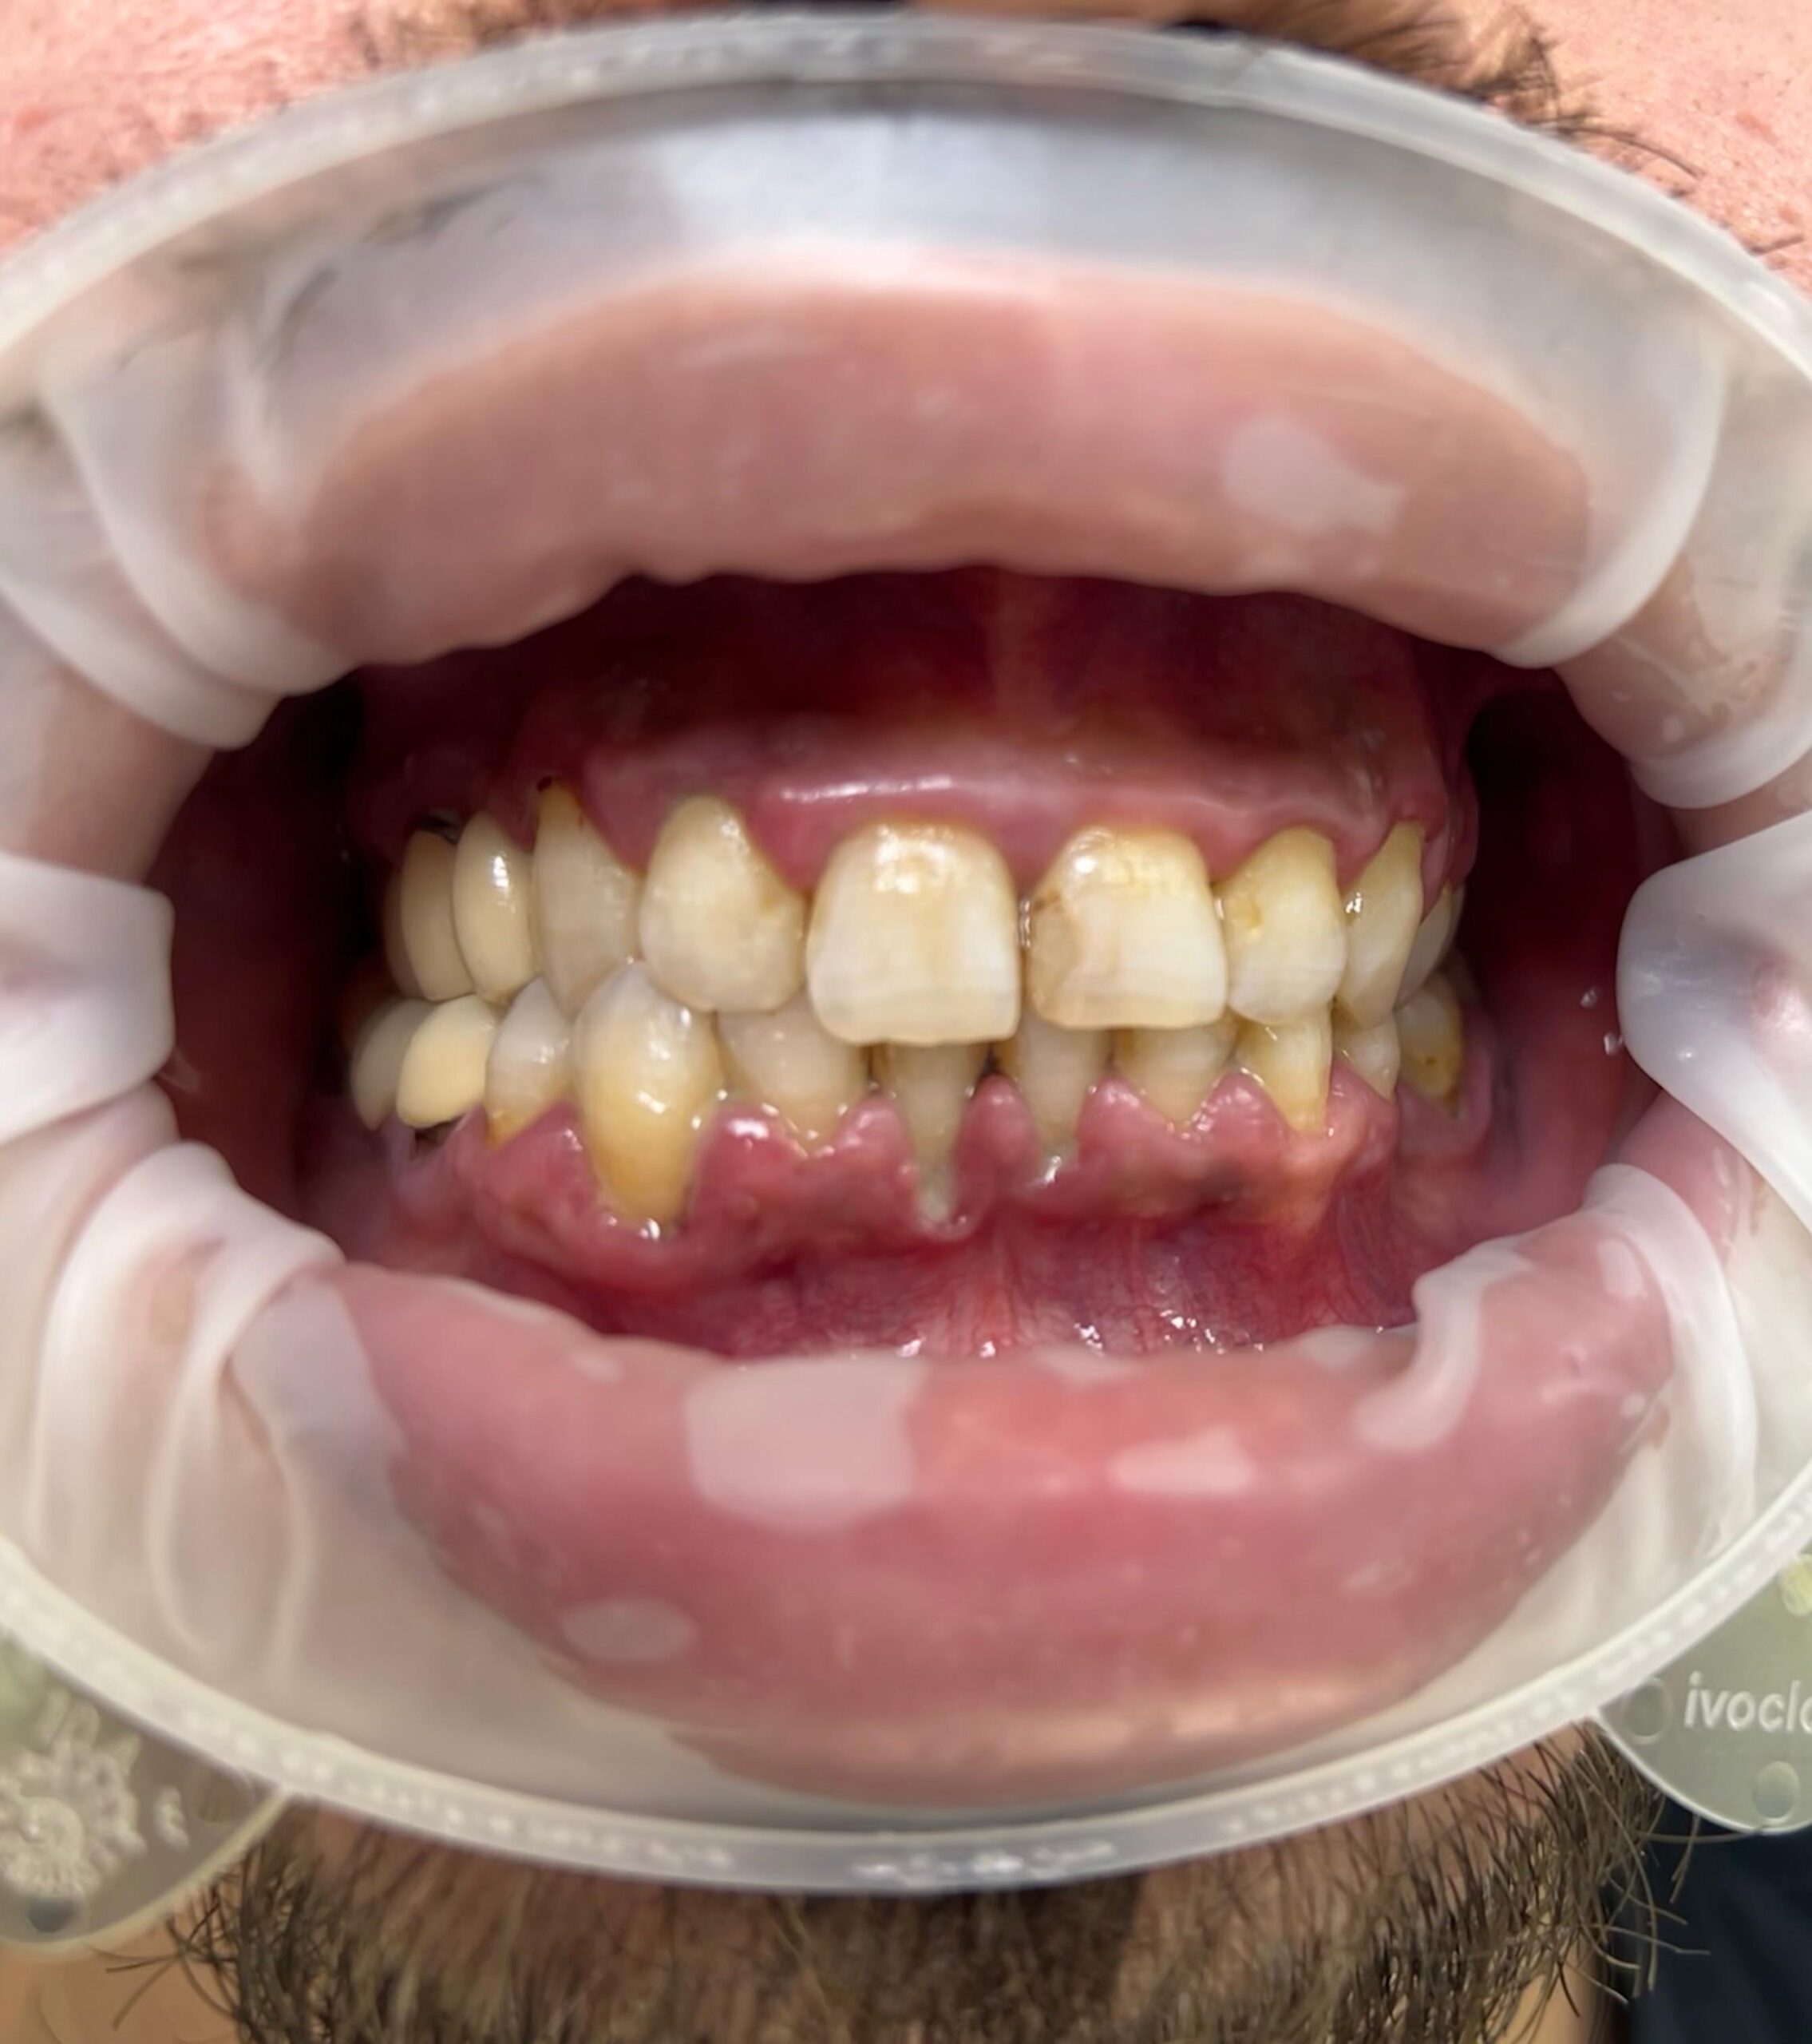

Parodontoza debutează adesea cu gingii roșii, umflate și care sângerează ușor la periaj sau folosirea aței dentare. Pe măsură ce boala progresează, pot apărea retracții gingivale, mobilitate dentară și respirație urât mirositoare. Dacă observi aceste semne, este esențial să consulți un specialist pentru un diagnostic și tratament adecvat.